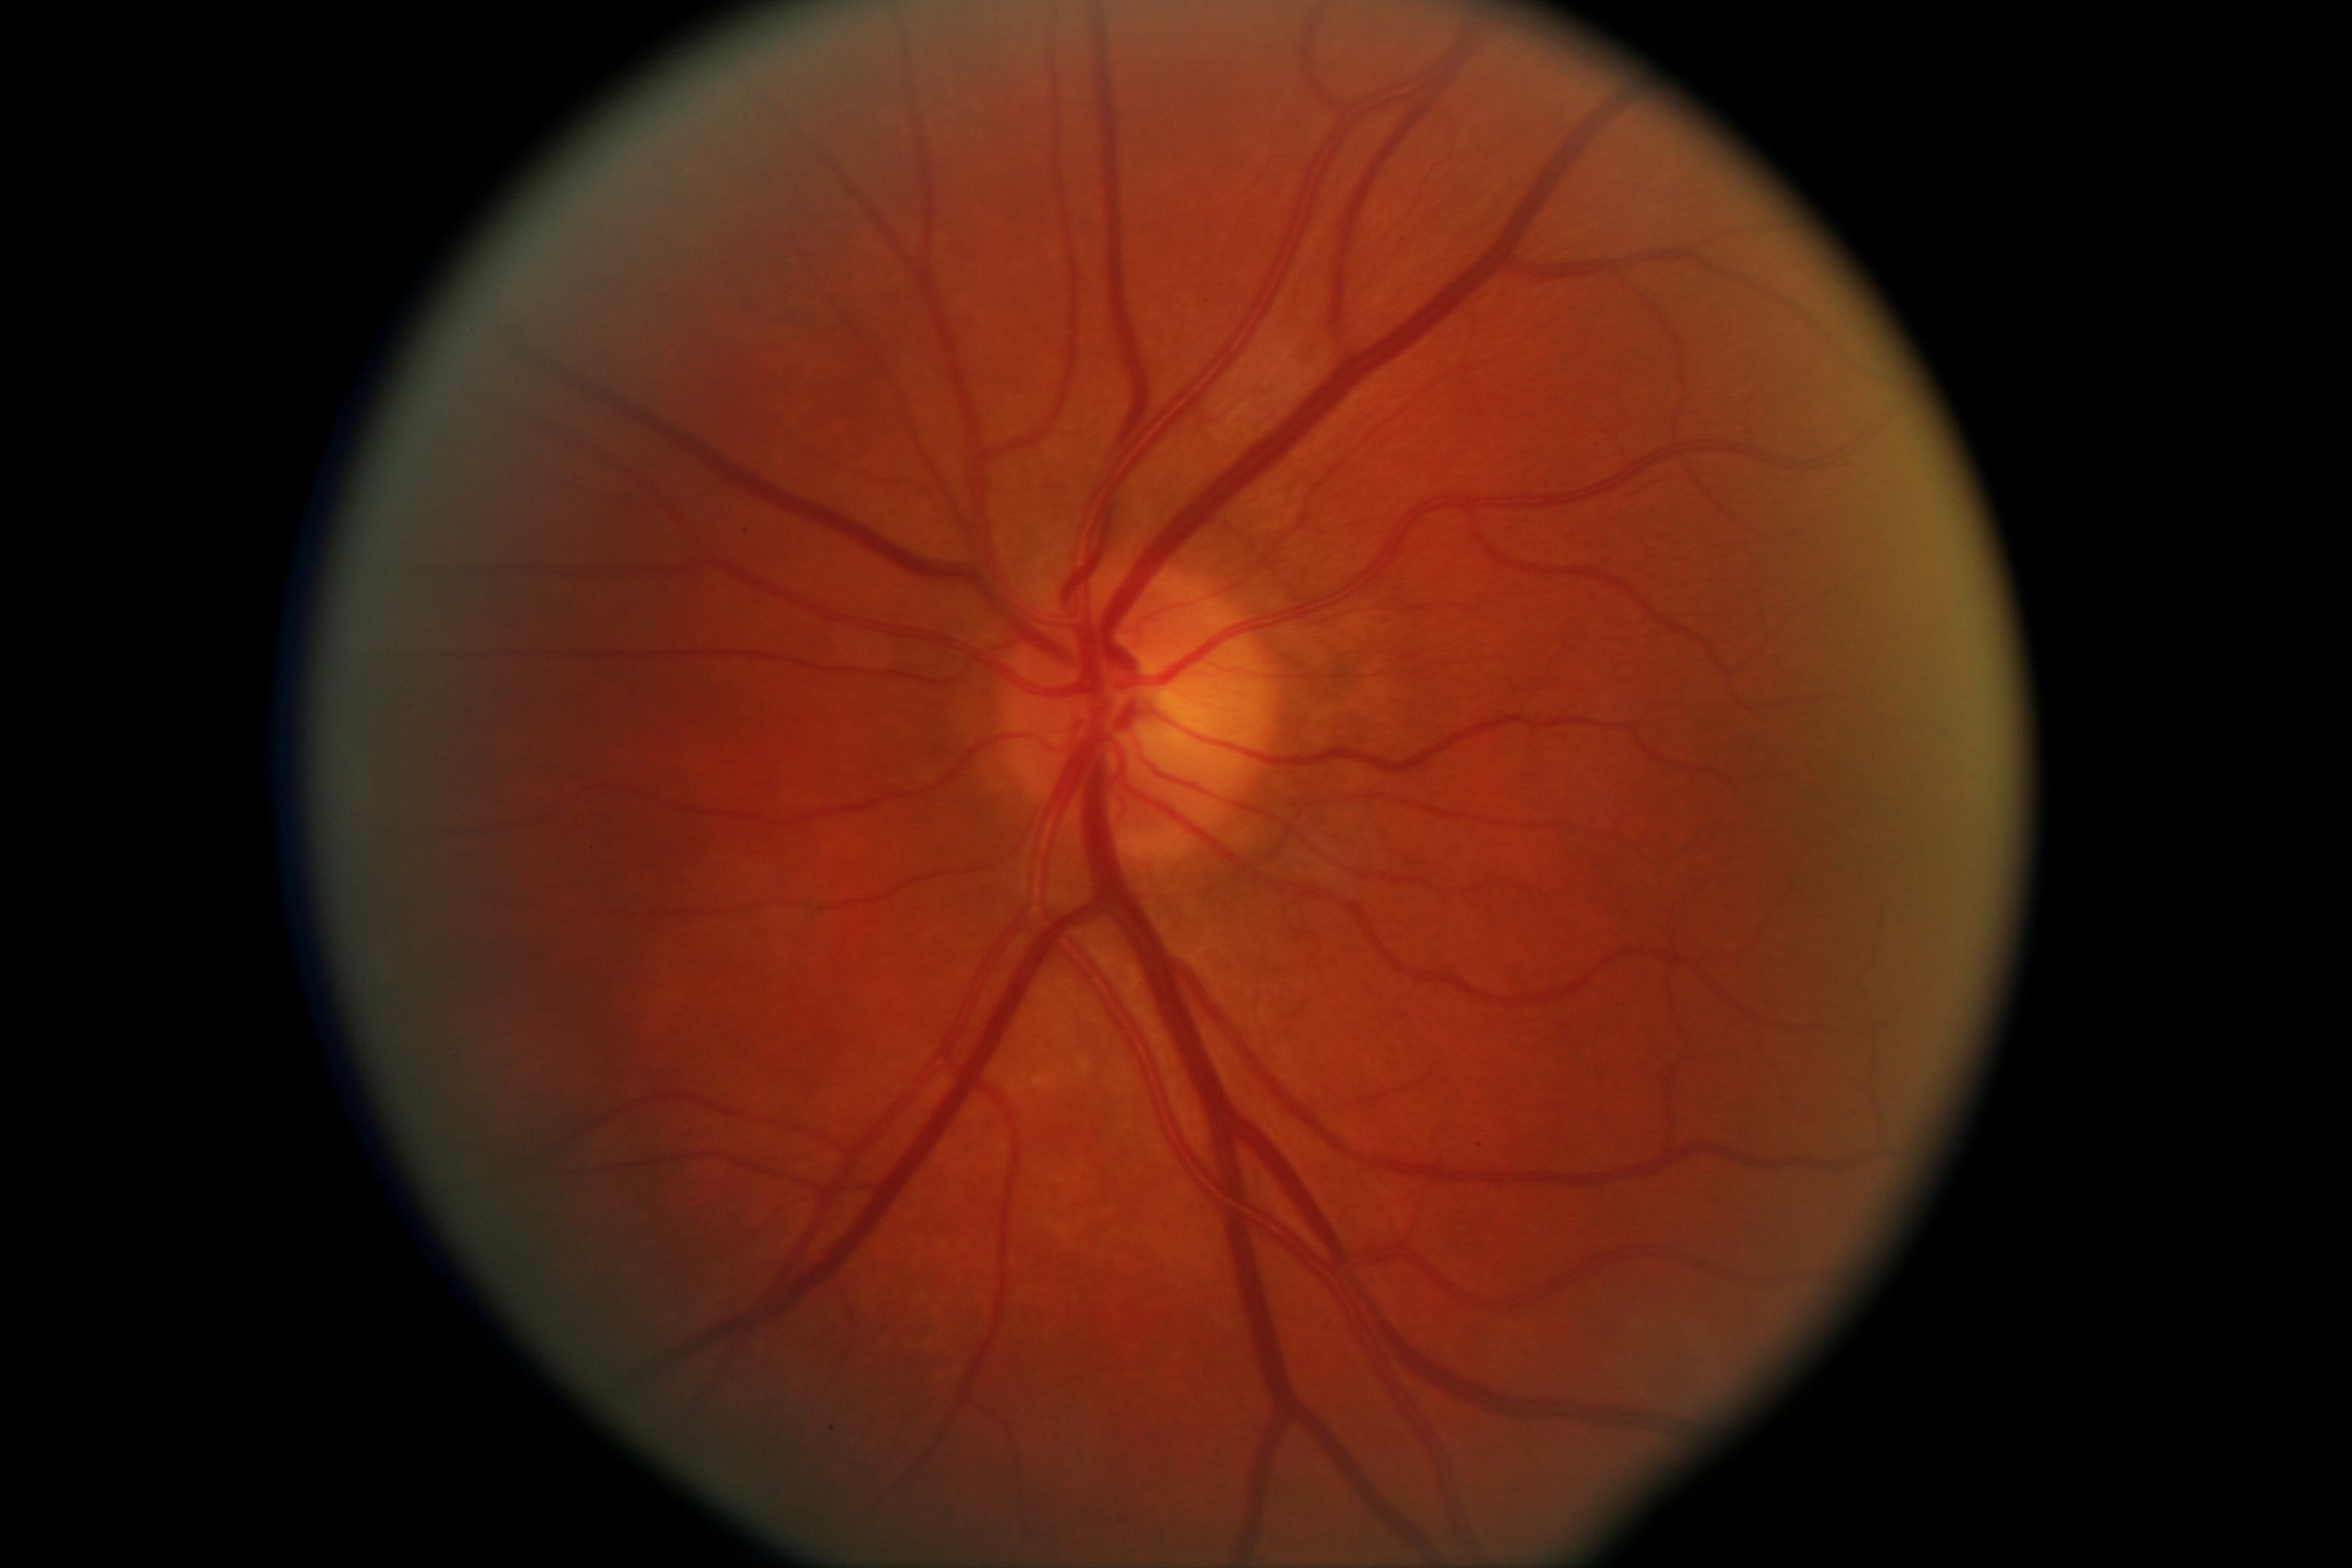

Атрофия зрительного нерва Лебера: Симптомы и лечение